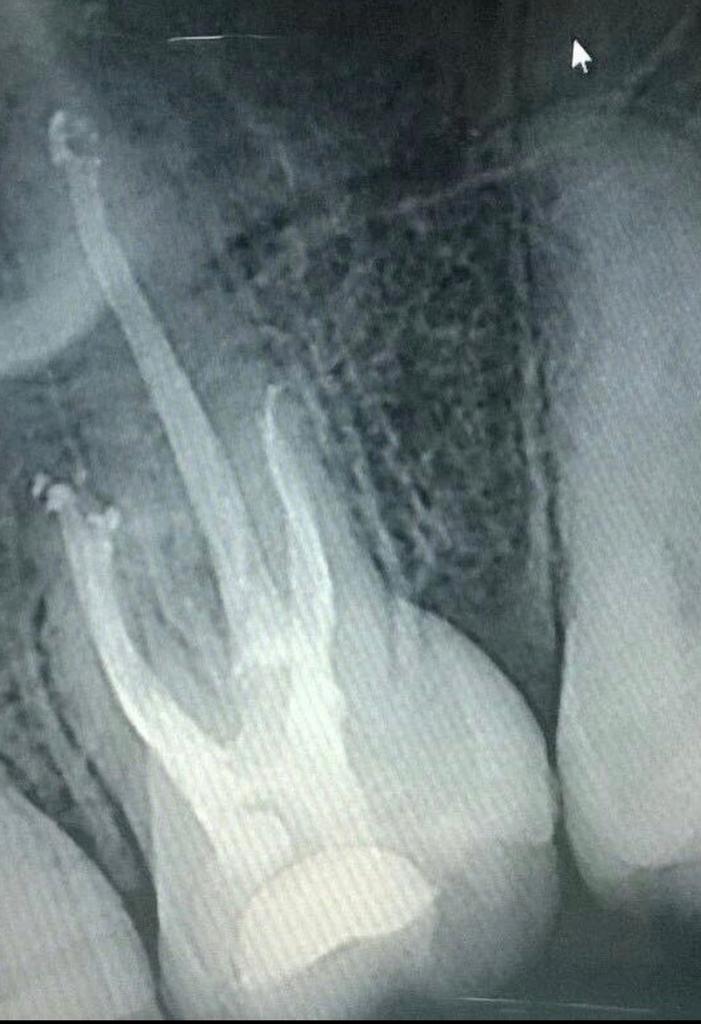

La Endodoncia o Tratamiento de Canal es el mejor procedimiento que puede realizarse en una clínica dental, ya que tiene como finalidad preservar las piezas dentales dañadas, causadas por lesiones inflamatorias en el interior del diente o pulpa dental, evitando así su pérdida. Para ello, se extrae la pulpa dental  (se encuentra en el interior del diente y contiene vasos sanguíneos, nervios y tejido conectivo). y la cavidad resultante, se rellena y sella con material totalmente biocompatible con los tejidos del diente.